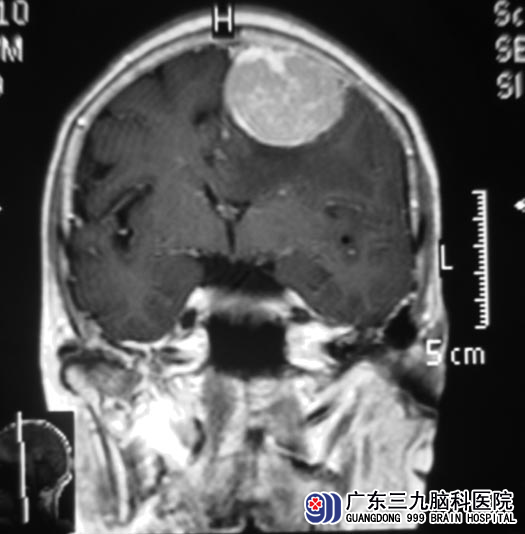

七十四岁的肖婆婆身体一直很好,可近一段时间出现胃口不佳,食欲差,最近三天总是频繁出现间断性头痛、恶心伴呕吐。家人非常重视,去医院检查,结果还真不是小问题,腹部B超检查提示肝内巨大囊肿,大小约80mm×63mm;头颅CT检查提示左侧额部大脑镰旁巨大占位,进一步MR检查显示占位大小5.66cm×5.66cm×3.20cm,左侧侧脑室体部受压、变窄,中线结构明显右移。http://www.999brain.com/

6月8日,广东三九脑科医院综合神经外科 鲁明主任主刀,在全麻下行左侧额部镰旁脑膜瘤切除术,术中见肿瘤位于硬膜下靠近大脑镰旁,呈灰黄色,质韧,血供丰富,边界清楚,先沿肿瘤内侧靠近大脑镰完全分离,再棉片保护肿瘤外侧脑组织,然后分块切除,最后完全切除肿瘤,手术顺利。手术后,肖婆婆头痛、恶心症状基本消失,没有出现任何并发症,可以自行下床活动。术后病理证实为:脑膜瘤(上皮型,WHO I级)。

▲手术前